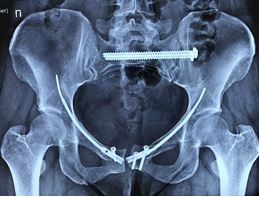

Также специалисты ЦТиО используют малоинвазивную методику при лечении переломов костей таза.

Переломы бедренной кости

Переломы бедренной кости часто сопровождаются массивной кровопотерей, что требует проведения оперативного вмешательства в кратчайшие сроки и с наименьшим повреждением мягких тканей. Отсутствие возможности передвигаться и вынужденный постельный режим чреваты развитием жизнеугрожающих осложнений со стороны органов дыхания, сердечно-сосудистой и пищеварительной систем.

Чаще всего встречаются переломы проксимального отдела бедренной кости: шейка бедра, вертельная области (чрезвертельные и подвертельные), диафизарные переломы и переломы дистального отдела бедренной кости. Больше всего им подвержены пожилые люди. Это связано с наличием остеопороза. В молодом возрасте эти переломы возникают вследствие высокоэнергетической травмы (падение, удар).

В ЦТиО ГВКГ им. Н.Н. Бурденко проводится огромный спектр оперативных вмешательств: от внутреннего остеосинтеза до эндопротезирования тазобедренного сустава. Специалисты центра травматологии и ортопедии способны решить данные проблемы путем применения высокотехнологичной малоинвазивной операции, продолжительностью не более 40 минут.

Доступ к больному участку производится через небольшие разрезы и под контролем рентгеновского аппарата. Методика интрамедуллярного малоинвазивного остеосинтеза позволяет избежать высокой кровопотери. Она также обеспечивает возможность ранней активизации больного, что очень важно у возрастных пациентов. Возраст самого пожилого пациента, прооперированного в ЦТиО ГВКГ им. Н.Н. Бурденко, составил 93 года.